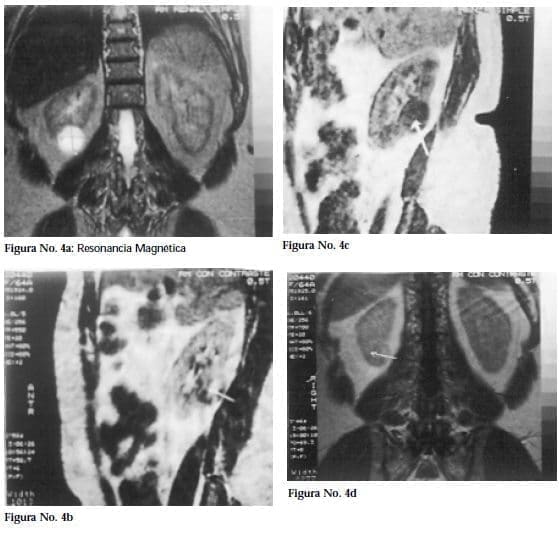

Como estos estudios imagenológicos no aclaraban el diagnóstico específico de la masa tumoral, se solicita una RM simple y contrastada que mostró un tumor sólido polar inferior del riñón derecho, CA renal estadio I según clasificación de Robson y además la posibilidad de corresponder a un oncocitoma